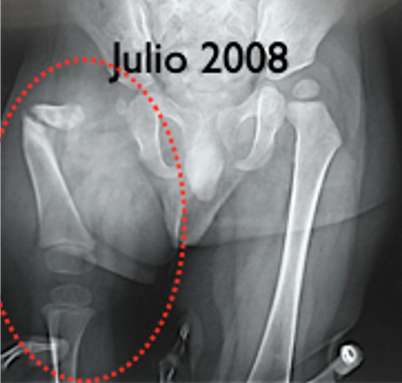

El tratamiento de la Pseudoartrosis Congénita de Tibia y Peroné (PCTyP) ha sido diverso. Todas las técnicas de tratamiento tienen una cuota de complicaciones, pero es la re-fractura y la falta de unión las principales consecuencias que se desean evitar. El objetivo de esta investigación se basa en analizar las técnicas quirúrgicas empleadas en nuestro centro y determinar los resultados. Se realizó un estudio retrospectivo, donde se estudiaron 11 pacientes con esta enfermedad con un seguimiento promedio de 4,73 años (DS±4,56). Todos los pacientes en quienes se utilizó la técnica de Charnley-Williams (CW) lograron la consolidación, la protección del clavo funcionó hasta que el extremo proximal de la tibia queda desprotegido al crecer el hueso y se produjeron angulaciones en esta zona, usualmente en la tibia proximal. Con el uso del clavo endomedular (EM) telescópico de Fassier-Duval (FD) se logra la protección de todo el hueso, inclusive durante el crecimiento. Se concluye que la técnica de CW es un buen método para la resolución de esta enfermedad y con el uso del clavo EM de FD se evita la refractura y se logra la unión permanente a medida que continúa el crecimiento del hueso. La discrepancia de los miembros inferiores es debida a la afectación de la tibia que compromete su crecimiento normal.